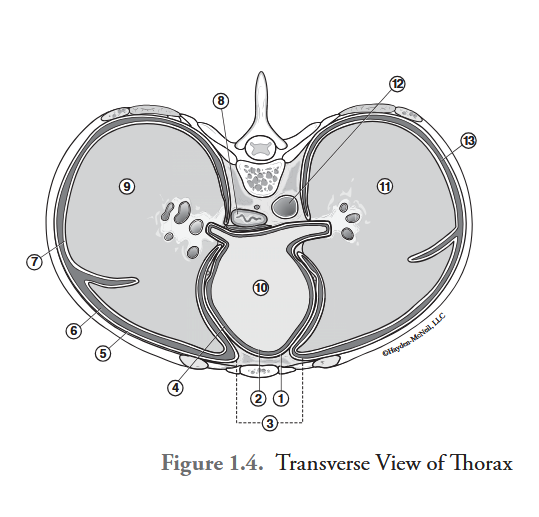

What is labeled #1?

parietal pericardium

What is labeled #2?

visceral pericardium (epicardium)

What is labeled #3?

mediastinum

What is labeled #4?

pericardial cavity

What is labeled #5?

parietal pleura

What is labeled #6?

right pleural cavity

What is labeled #7?

visceral pleura

What is labeled #8?

esophagus

What is labeled #9?

right lung

What is labeled #10?

heart

What is labeled #11?

left lung

What is labeled #12?

descending aorta

What is labeled #13?

left pleural cavity